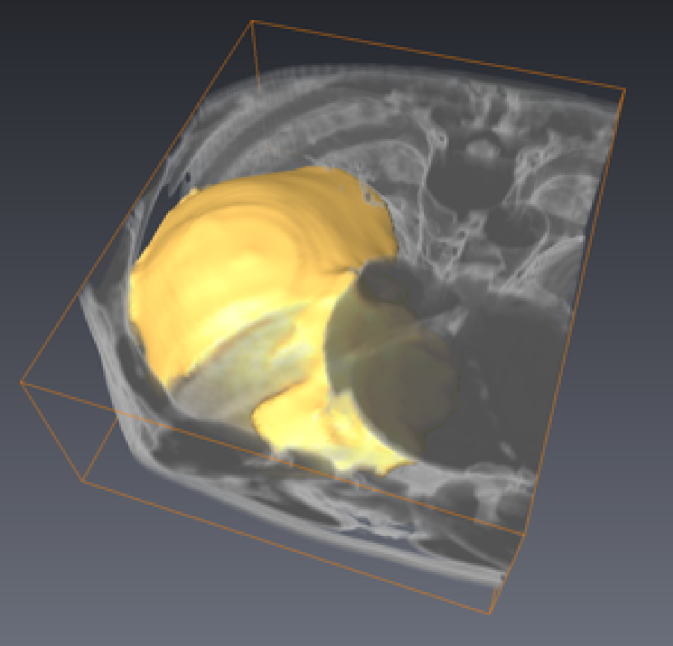

4.4.3 3D segmentation

|

For 3D image segmentation, the minimal surface properties of CCMF generate good quality results, as shown in Fig 10. The CCMF formulation applies equally well in 2D or 3D, since CCMF is formulated on an arbitrary graph (which may be a 2D lattice, a 3D lattice or an even more abstract graph). In 3D, our CCMF implementation is suffering from memory limitations in the direct solver we used, limiting its performances. Future work will address this issue using a dedicated solver.